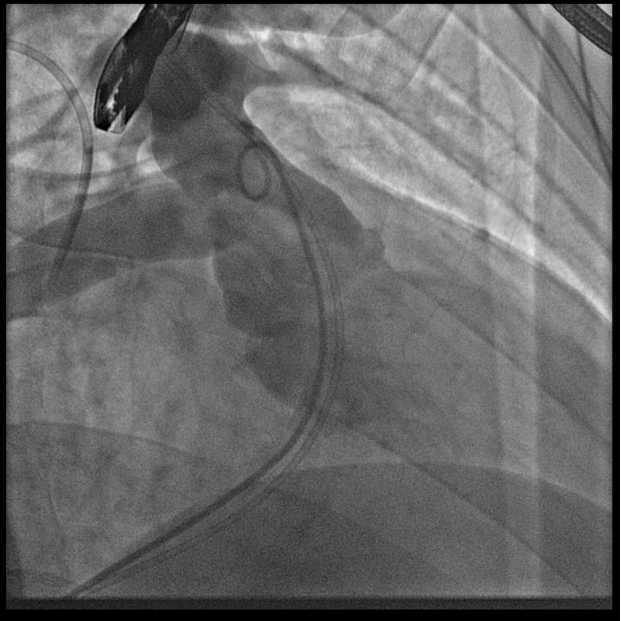

葛院士团队评估后认为,患者右肺动脉因阻挡存在狭窄,且右肺动脉与主肺动脉压差较大,具有临床意义,存在解决的必要。先后尝试Snare圈套瓣架下缘下拉法、双导管圈套瓣架上缘下拉法,但效果不理想,复测右肺动脉与主肺动脉压差仍较大,选择性右肺动脉造影仍存在右肺动脉狭窄。但考虑到患者利益,在安全操作的基础上,团队仍未放弃。拟通过将球囊送至右肺动脉开口处扩张,达到下压瓣膜支架、解除右肺动脉狭窄的效果,考虑到该操作的难点在于球囊无法顺畅到达肺瓣上目标位置,决定采用简略版PASS技术,即通过辅路送Snare至右肺动脉开口,并利用该Snare圈套住主路的Lunder quist导丝,换言之,即通过Lunder quist导丝两头发力将三尖瓣-右室流出道-右肺动脉这一扭曲的途径直线化且增强Lunder quist导丝支撑力,同时,由于Lunder quist导丝在右肺动脉处有附着力,可以避免瓣膜下移过多,如此球囊顺利通过瓣膜支架网孔进入右肺动脉,在DSA指引下逐步扩张球囊,成功使人工瓣膜支架向右心室侧移位。复查造影提示右肺动脉开口未见明显阻挡(图五),复测主肺动脉、左肺动脉、右肺动脉压力分别为32/9/19mmHg、32/7/18mmHg、29/7/17mmHg。复查肺动脉主干造影,显示人工瓣膜启闭良好,轻微瓣膜反流。最终手术疗效显著、取得令人满意的结果。

图五:通过PASS技术将球囊送至右肺动脉开口并扩张球囊、完成肺动脉瓣膜支架向心室侧移位,复查造影右肺动脉未见明显阻挡